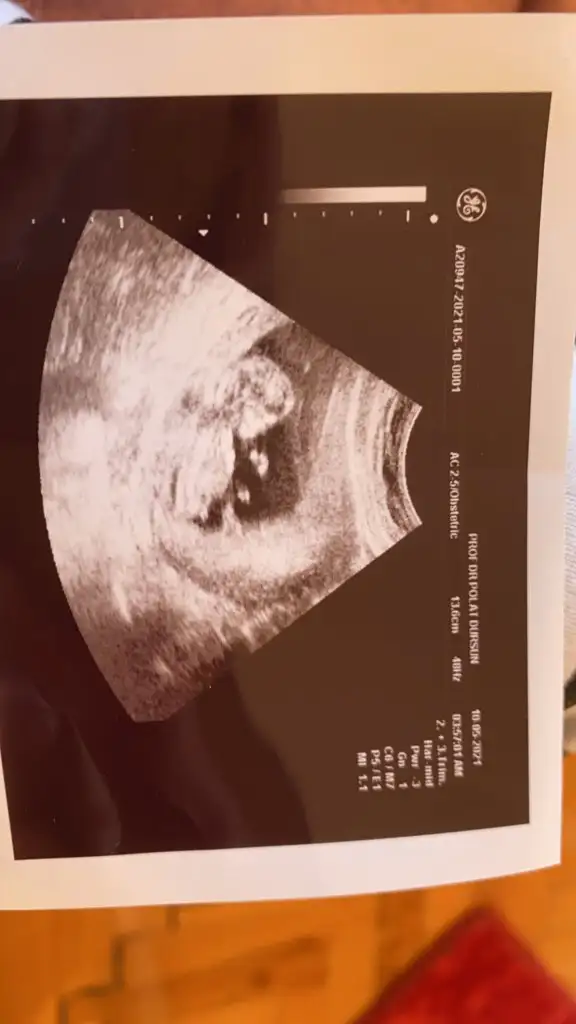

Anliyorsan ultrason resmi atabilir miyim11-13 hafta araligindaki ultrason fotosundan, bebegin genital bolgesindeki cikintiya bakiliyor, orda cikinti dumduz ise kiz, yukari dogru ise erkek olarak yorumlanıyor

Bende erkek gibi hissettimCinsiyet tahmininden hiç anlamıyorum. Dün doktor henüz bir şey demek için erken dediAcaba tahminleriniz ne olur. Bana burnu falan kız gibi geldi ama

Canım çok anladigim soylenemez ama atarsan hepimiz bir yorum yaparız isteAnliyorsan ultrason resmi atabilir miyim